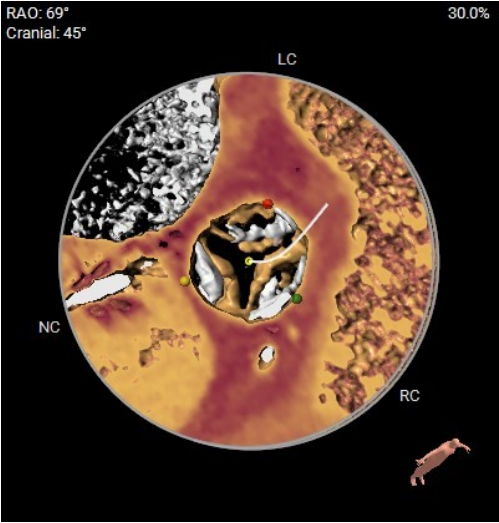

术中影像

1.主动脉根部造影,可见大量反流

2.输送系统过主动脉弓

3.输送系统造影定位

4.释放瓣膜

5.瓣膜完全释放

6.最终造影,反流消失

手术结果

术后食道超声及造影未见瓣周漏,效果良好,手术圆满完成。

瓣膜释放后,食道超声及造影均提示瓣膜无残余反流。